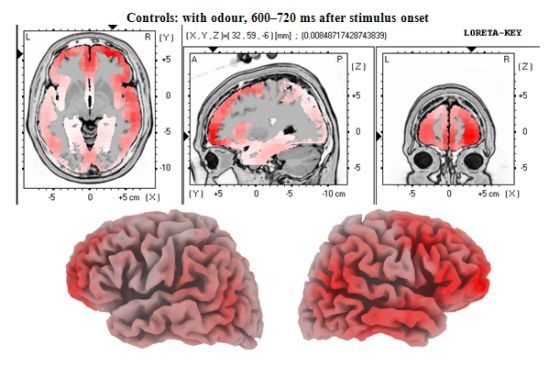

3.2. EEG Data

4.2. Electrophysiology